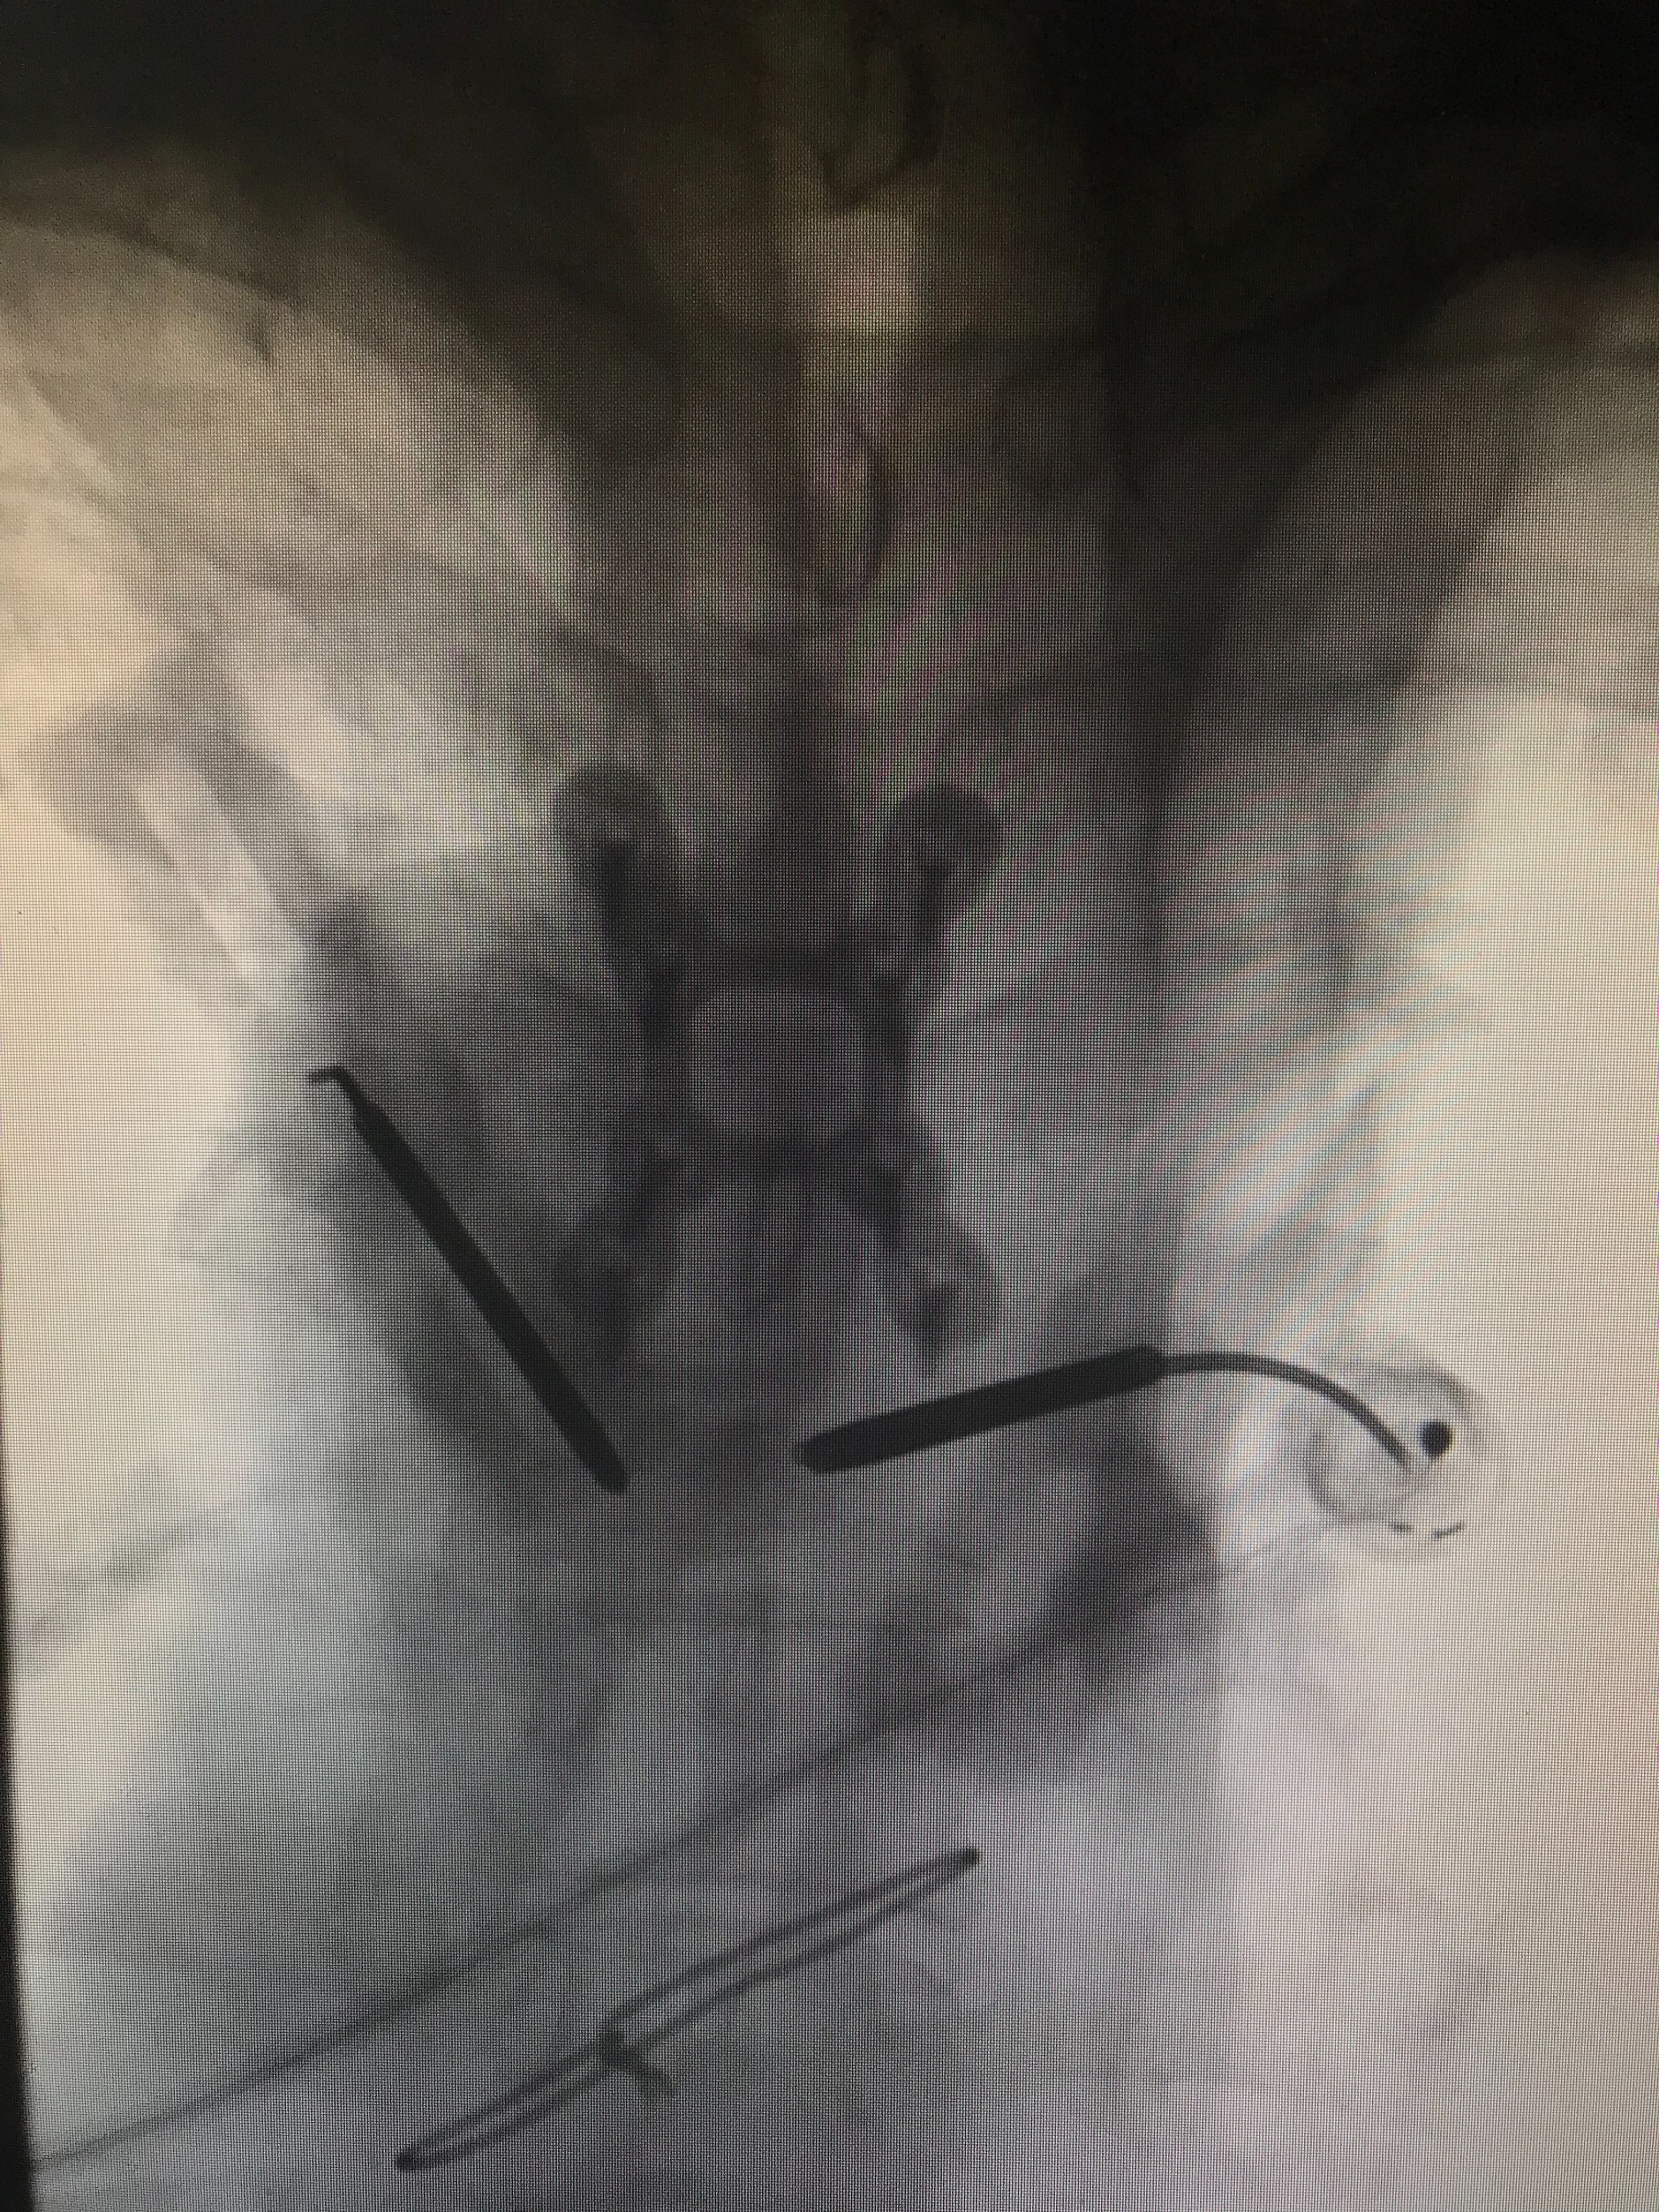

DSA引导下双侧椎弓根入路置针成功(侧位)

DSA引导下双侧椎弓根入路置针成功(正位)

单针射频消融椎体肿瘤(正位)

单针射频消融椎体肿瘤